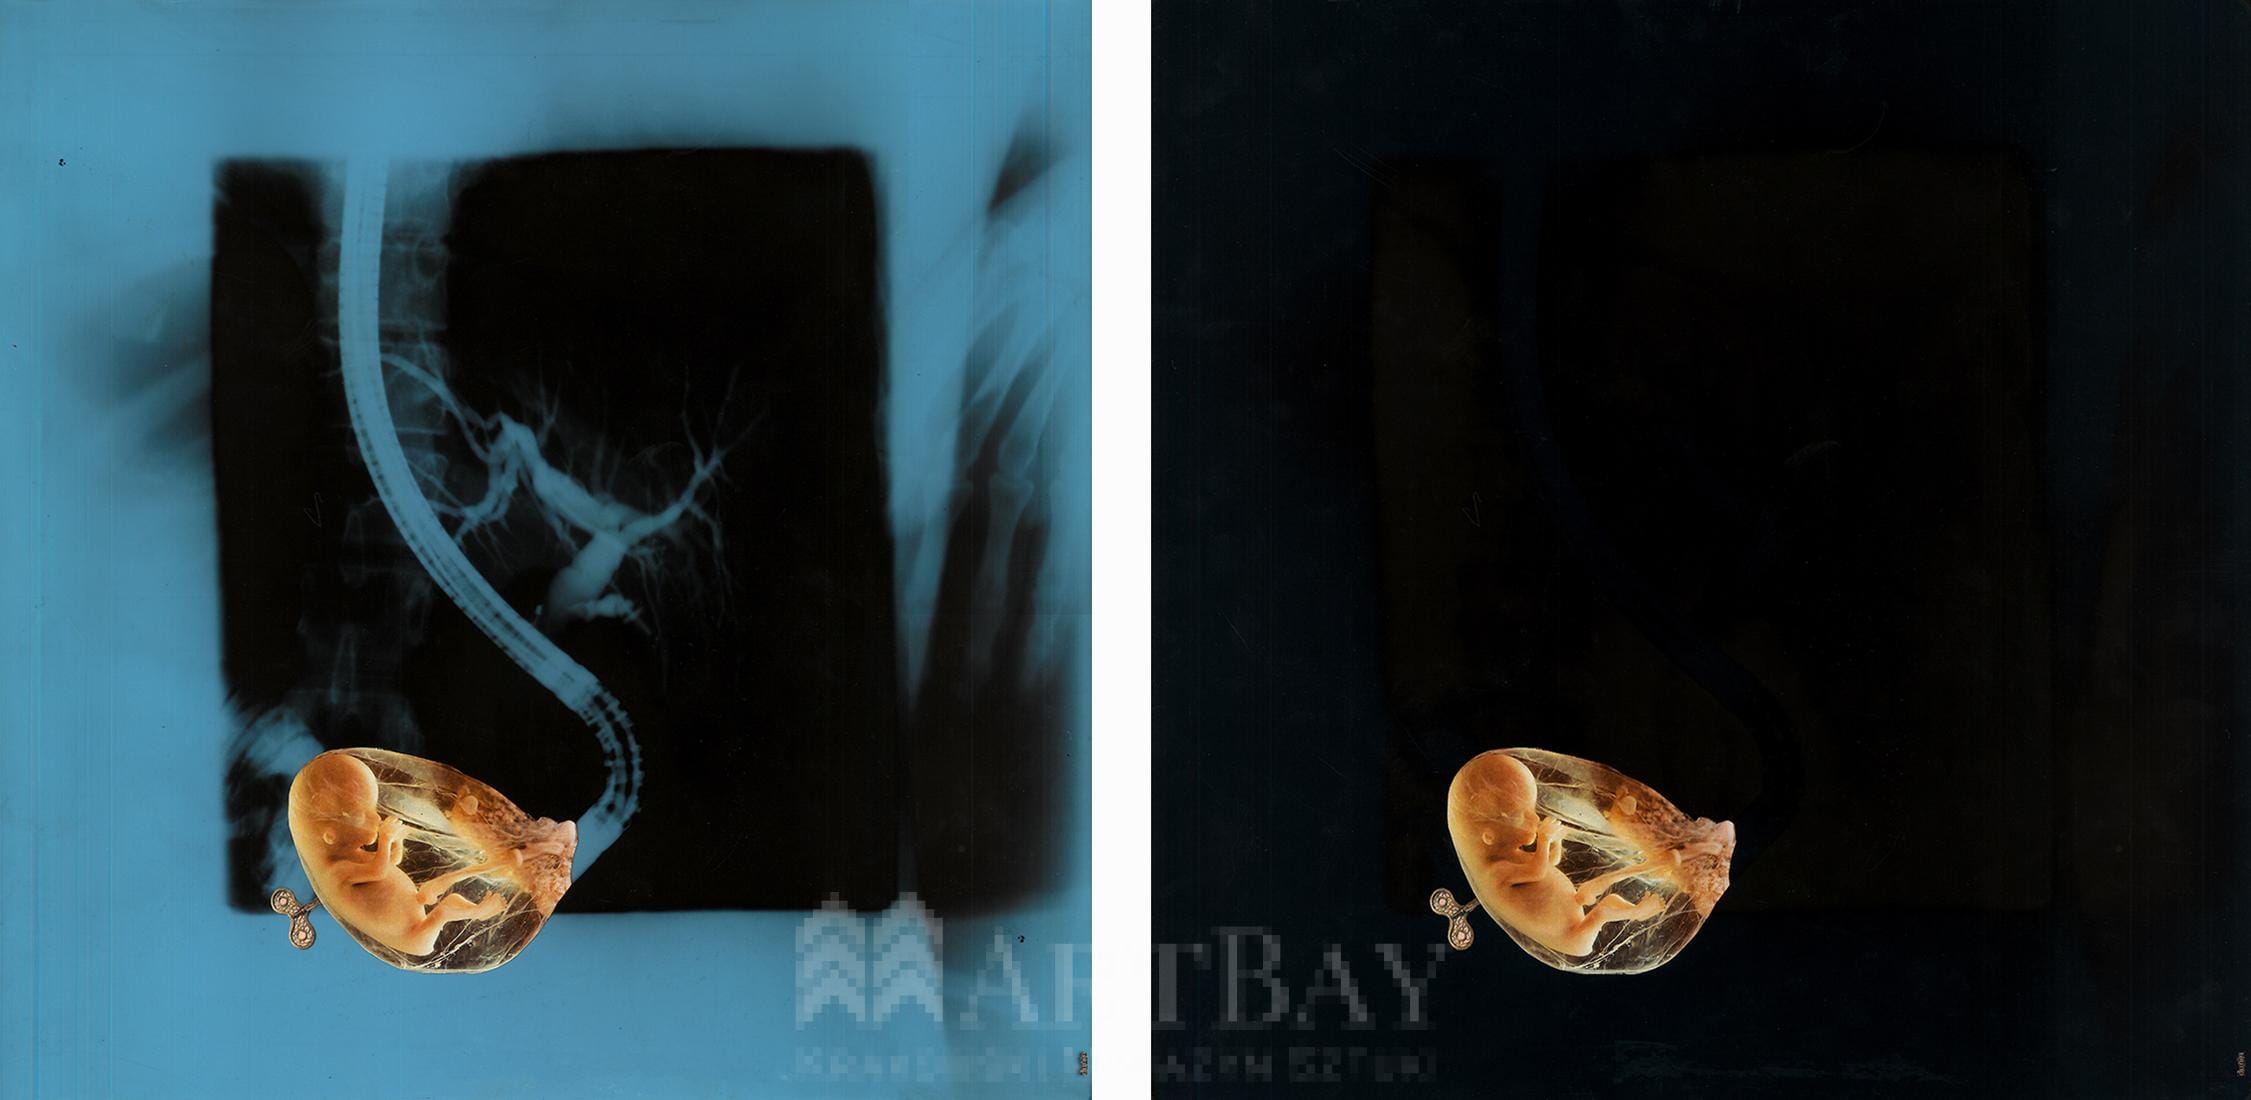

Ephemerality IV

Zakres cen: od 162,00 zł do 402,00 zł

| Wariant produktu | Fine Art, Kopia na płótnie |

| Rozmiar | L 50×70, M 40×50, S 30×40 |

Praca wykonana w technice kolażu, w kolorystyce czerni, niebieskiego oraz kontrastowej żółci.

| Rok wykonania: | 2021 |

| Technika: | Kolaż |

| Temat: | Człowiek |

| Podłoże: | Papier |